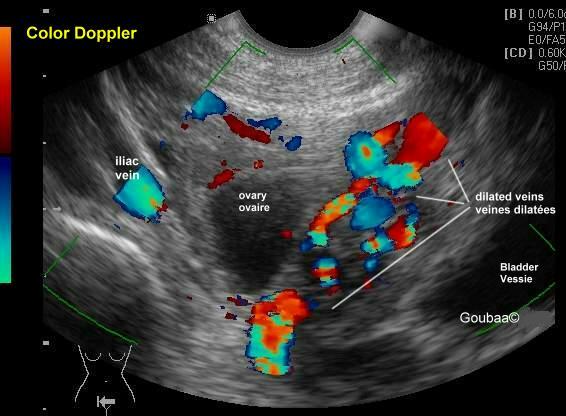

顾名思义,不过是盆底静脉迂曲扩张,由于在深处,只有少部分患者会有会阴、臀部及大腿静脉曲张的外在表现,单纯静脉曲张还好,对生活质量影响小,如果曲张严重就会产生一系列的临床表现,尤其是慢性的腹部不适,医学上有术语叫做盆腔瘀血综合征。

盆腔淤血综合征其实是盆腔曲张基础上出现,而盆腔的静脉丛特别丰富,曲张最为多发的是左侧的卵巢静脉。左侧容易出现曲张的原因主要是因为人体特殊的解剖构造所决定的,而女性更为高发则是因为怀孕过程增加了本病的发生机会。男性当然也有,只是比较少见,主要表现出精索静脉曲张。

静脉造影虽然属于金标准,但是毕竟有创伤存在,不适合进行病人的筛查。而超声因为其无创性,是一个很有效的筛查手段,可以提供血管的动态指标,提示血管的直径和流速,但是对超声医生的要求比较高。CT和核磁检查显现比较立体,更受青睐,需要体内注射一些对比剂。当然也有一些报道会采用腹腔镜探查的方式来判断,但是单纯因为可耐受的慢性腹痛去做这个手术,并不受待见。